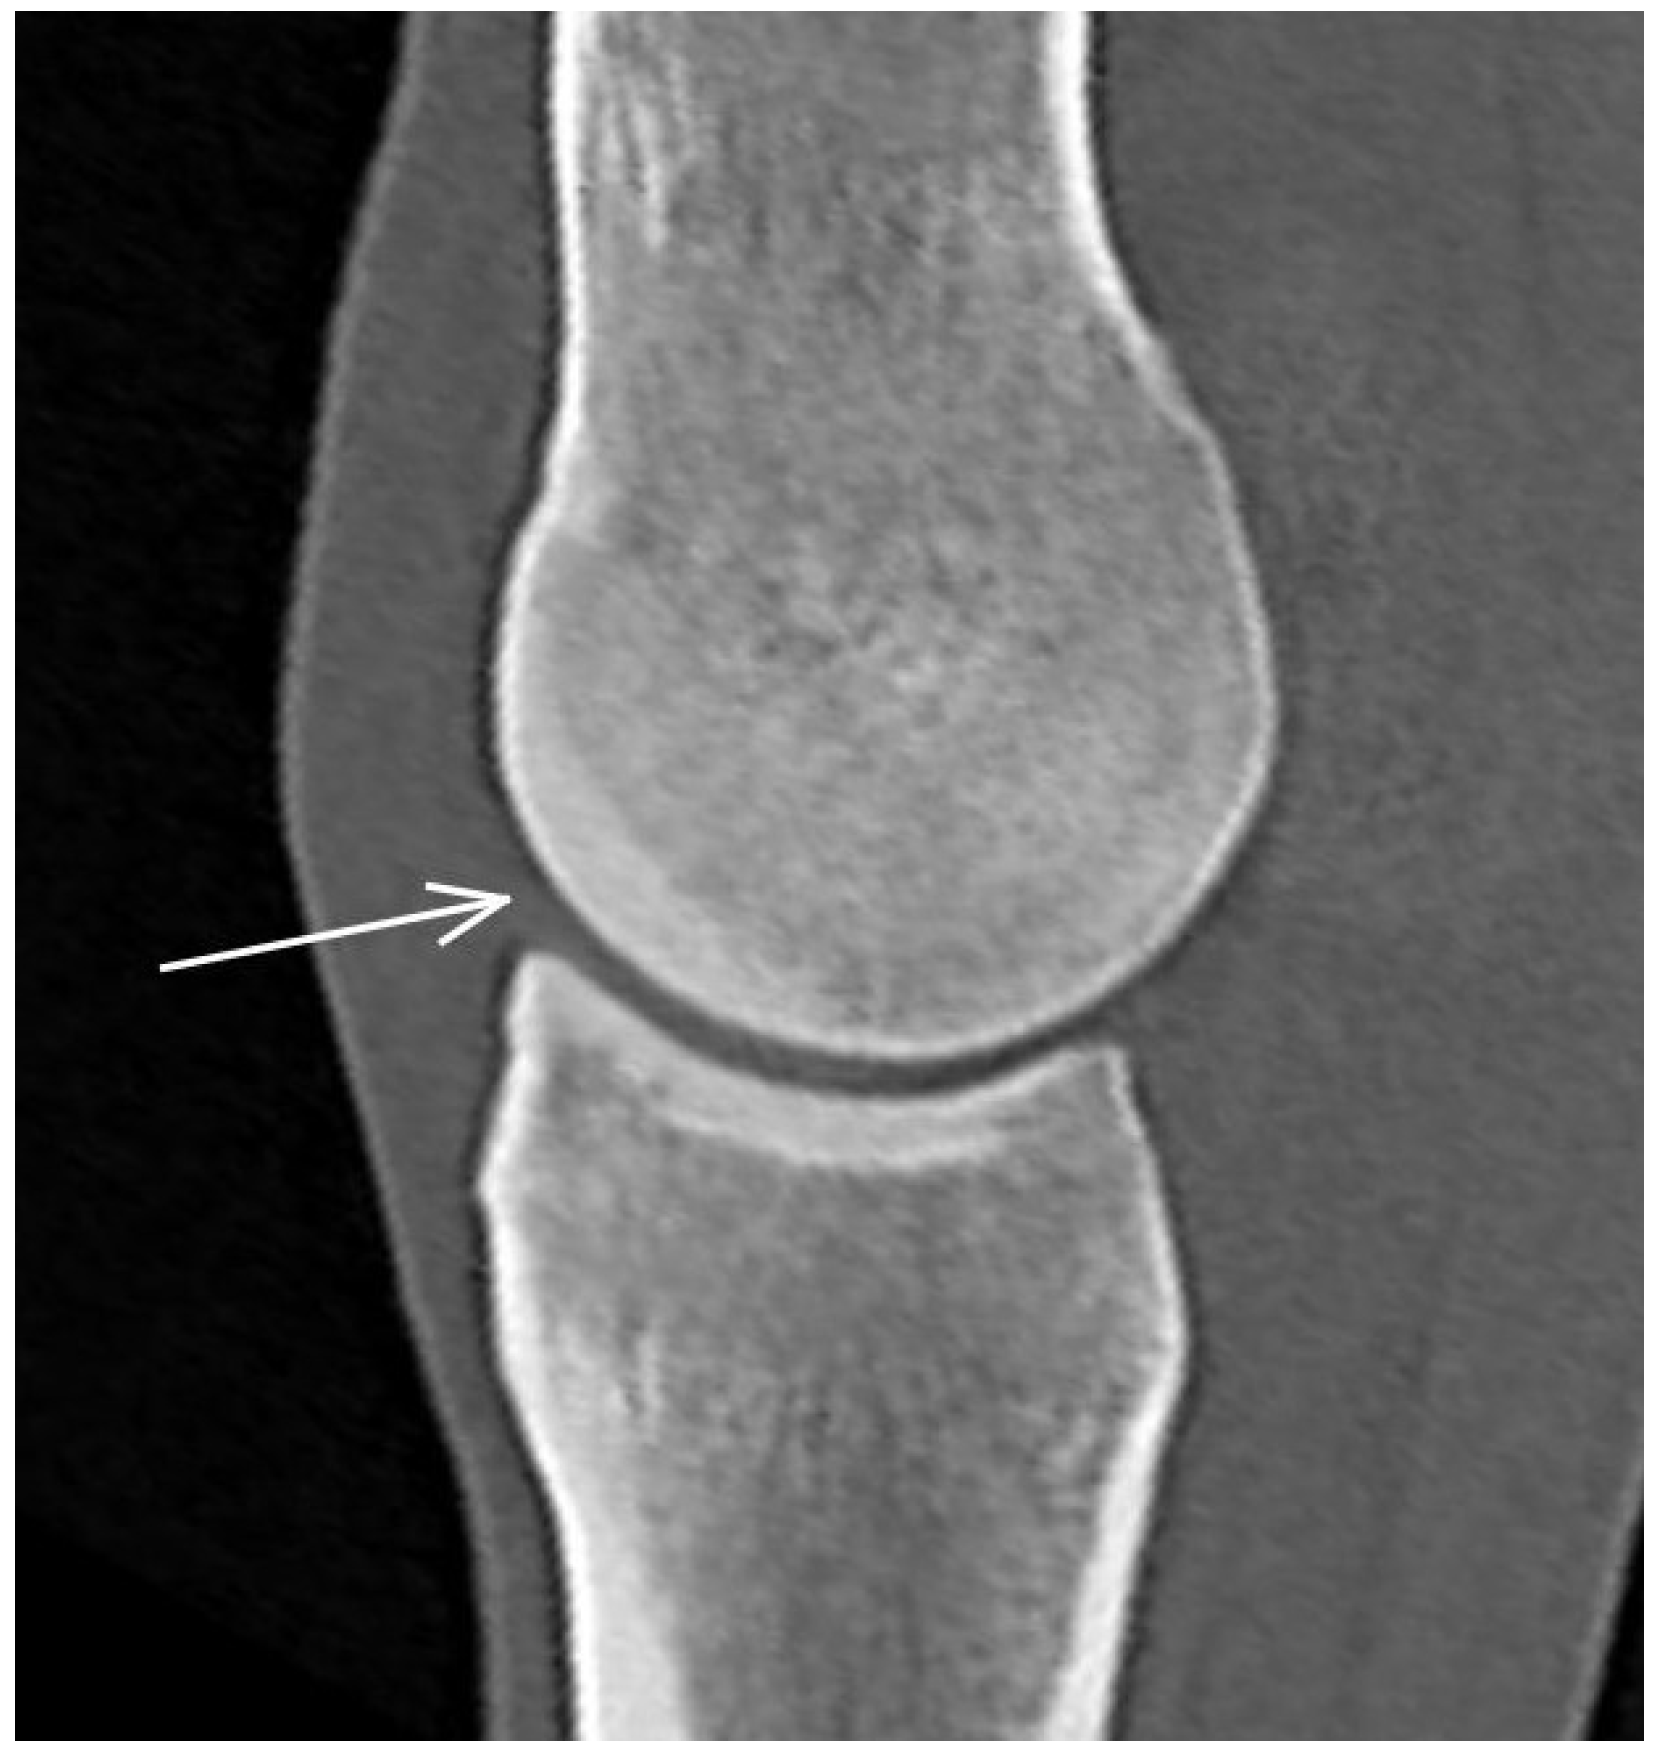

3.1. The Third Metacarpal Bone (McIII)

| Medial/lateral condyle | |||

| Subchondral bone thickening Dorsal/palmar half Increased attenuation in the trabecular bone Dorsal/palmar half Hypoattenuating lesion in the subchondral bone Location | Subchondral bone thickening Dorsal/palmar half Decreased signal intensity in the trabecular bone Dorsal/palmar half Increased signal intensity in the subchondral bone Location | Increased opacity in the trabecular bone Lucent lesion in the subchondral bone Location | |